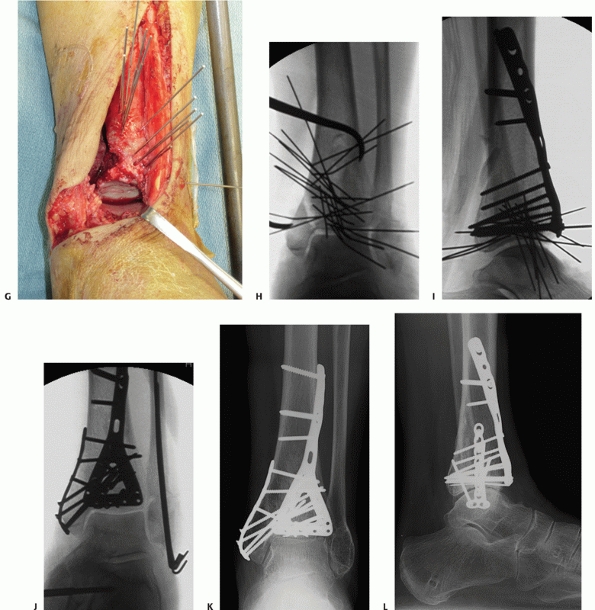

FIGURE 56-13 Injury anteroposterior (A) and lateral (B)

radiographs of a 32-year-old man involved in a moderate speed motor vehicle collision. The lateral radiograph demonstrates marked displacement of the posterolateral fragment from the distal tibia (C,D). Although markedly improved after fibular reduction via a posterolateral incision, substantial residual displacement of the posterolateral articular surface (*) remains. The white arrow denotes an impacted central plafond fragment. Provisional (E) and definitive (F) fixation of the posterolateral articular fragment performed using the posterolateral surgical incision. (continues) |

![]() |

FIGURE 56-13 (continued) At the conclusion of fixation, the distal tibia was managed with spanning external fixation (G-I).

After resolution of soft tissue swelling, the remainder of the tibial plafond was reduced and stabilized using a modified anteromedial approach. (continues) |